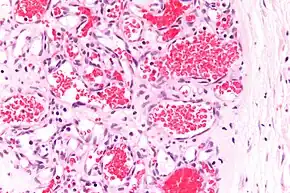

A precise history of the growth characteristics of the IH can be very helpful in making the diagnosis. In the first 4 to 8 weeks of life, IHs grow rapidly with primarily volumetric rather than radial growth. This is usually followed by a period of slower growth that can last 6–9 months, with 80% of the growth completed by 3 months. Finally, IHs involute over a period of years.[34] The exceptions to these growth characteristics include minimally proliferative His, which do not substantially proliferate[33] and large, deep IHs in which noticeable growth starts later and lasts longer.[34] If the diagnosis is not clear based on physical examination and growth history (most often in deep hemangiomas with little cutaneous involvement), then either imaging or histopathology can help confirm the diagnosis.[31][35] On Doppler ultrasound, an IH in the proliferative phase appears as a high-flow, soft-tissue mass usually without direct arteriovenous shunting. On MRI, IHs show a well-circumscribed lesion with intermediate and increased signal intensity on T1- and T2-weighted sequences, respectively, and strong enhancement after gadolinium injections, with fast-flow vessels.[31] Tissue for diagnosis can be obtained via fine-needle aspiration, skin biopsy, or excisional biopsy.[36] Under the microscope, IHs are unencapsulated aggregates of closely packed, thin-walled capillaries, usually with endothelial lining. Blood-filled vessels are separated by scant connective tissue. Their lumina may be thrombosed and organized. Hemosiderin pigment deposition due to vessel rupture may be observed.[37] The GLUT-1 histochemical marker can be helpful in distinguishing IHs from other items on the differential diagnosis, such as vascular malformations.[32]